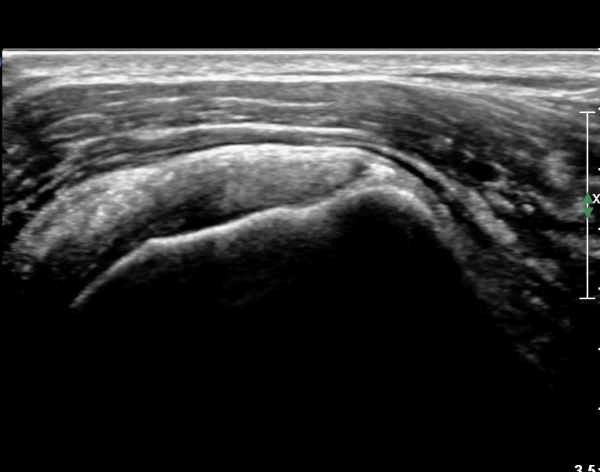

ÃÊÀ½ÆÄ ¼Ò°ß :  ÀÌµÎ¹Ú±Ù°Ç È¾´Ü¸é°Ë»ç¿Í ±Ø»ê°Ç Á¾´Ü¸é°Ë»ç¿¡¼­  ƯÀÌ ¼Ò°ß ¾øÀ½(»çÁø 1, 2).